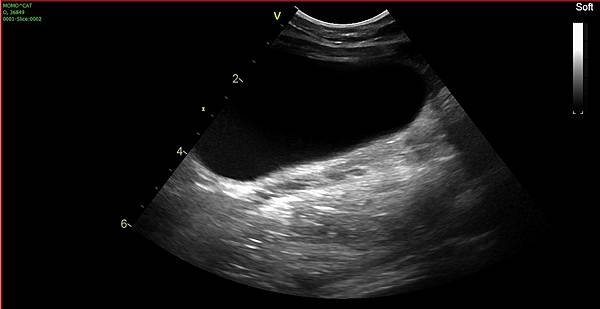

醫生一掃小雪的腎臟

對於嚴重的囊泡是一陣驚呼,還蠻嚴重的...

肝臟囊泡變多了也變嚴重了,約有四個小囊泡→去年以往只有一顆

雙側的腎臟囊泡也變嚴重,現在已經無法計算大小和數量了

左腎大小6cm

右腎大小4cm

兩側都有血流,右腎狀況明顯比左側好